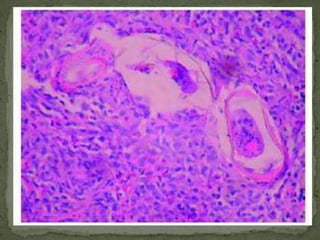

Toxoplasma gondii cyst in brain tissue stained with hematoxylin and eosin (100×).

CystercercosisSymptoms depend on location of cysts, but frequently include motor spasms, seizures, confusion, irritability, and personality changeIn the eye, often subretinal or in vitreous.  Movement may be seen by the patient.  Pain, amaurosis, and loss of vision may occur.

CysticercosisClinical manifestationsAdult worms rarely cause sxsLarvae penetrate intestine, enter blood, and eventually encyst in the brain.Cerebral ventircles  hydrocephalusSpinal cord  compression, paraplegiaSubarachnoid space  chronic meningitisCerebral cortex  seizuresCysts may remain asymptomatic for years, and become clinically apparent when larvae dieLarvae may encyst in other organs, but are rarely symptomatic

CysticercosisDiagnosisCT and MRI preferred studiesDiscrete cysts that may enhanceUsually multiple lesionsSingle lesions especially common in cases from IndiaOlder lesions may calcifyCSFLymphs or eos, low glucose, elevated proteinSerologyEspecially in cases with multiple cysts